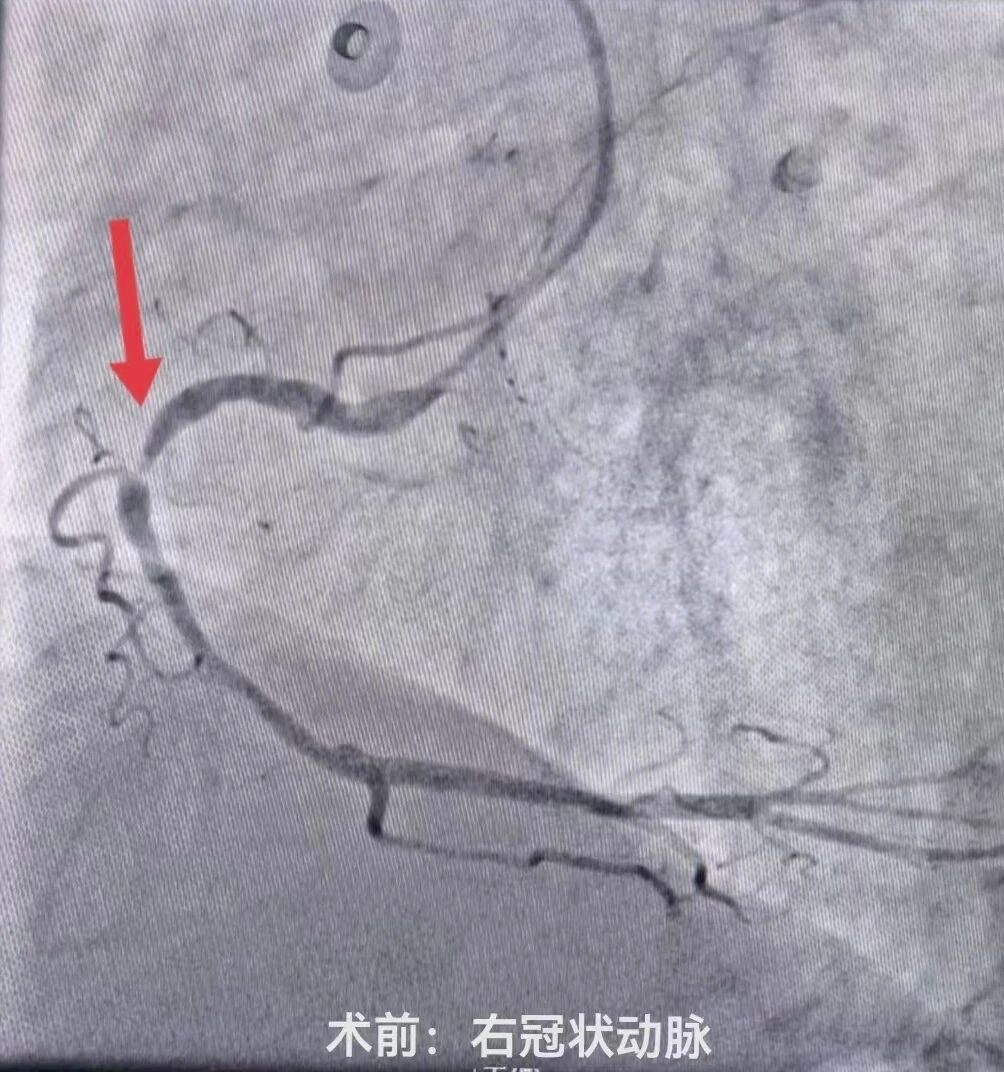

介入室内,医护团队严格遵循标准化操作流程,消毒、穿刺、造影等步骤一气呵成。冠状动脉造影显示心脏三支血管均有严重狭窄,其中两根主要血管均有95%以上的堵塞,患者已出现心力衰竭表现,生命危在旦夕,只有一次性处理两处严重狭窄病变才能为患者带来生的希望。刘晓建主任带领的介入团队凭借丰富的临床经验和精湛的介入技术预判手术风险,勇担重任,术中认真仔细操作,快速高效的同时完成了左前降支(LAD)、右冠状动脉(RCA)球囊扩张及支架植入术。随着支架成功释放,闭塞的血管瞬间恢复通畅,心肌供血得以重建,患者胸闷、胸痛症状较前明显缓解,生命体征逐渐平稳。

术前术后对比